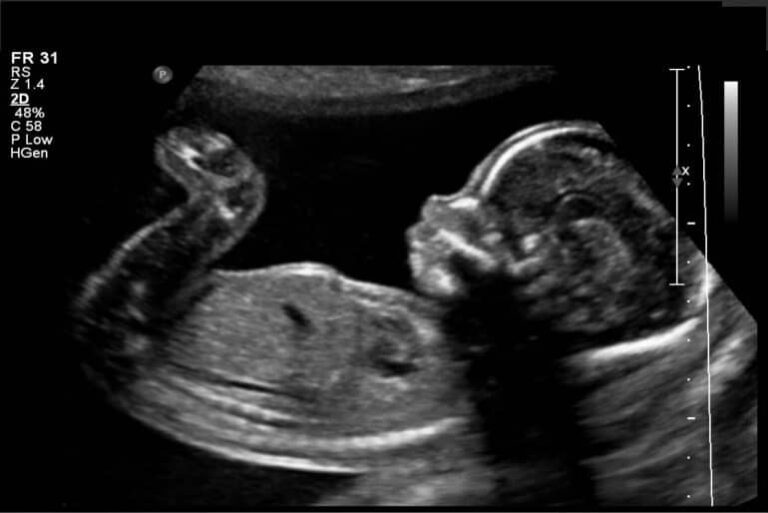

Avaliação da vitalidade fetal anteparto

O contexto atual da atividade médica exige do obstetra e ginecologista ampla compreensão dos avanços científicos e tecnológicos…